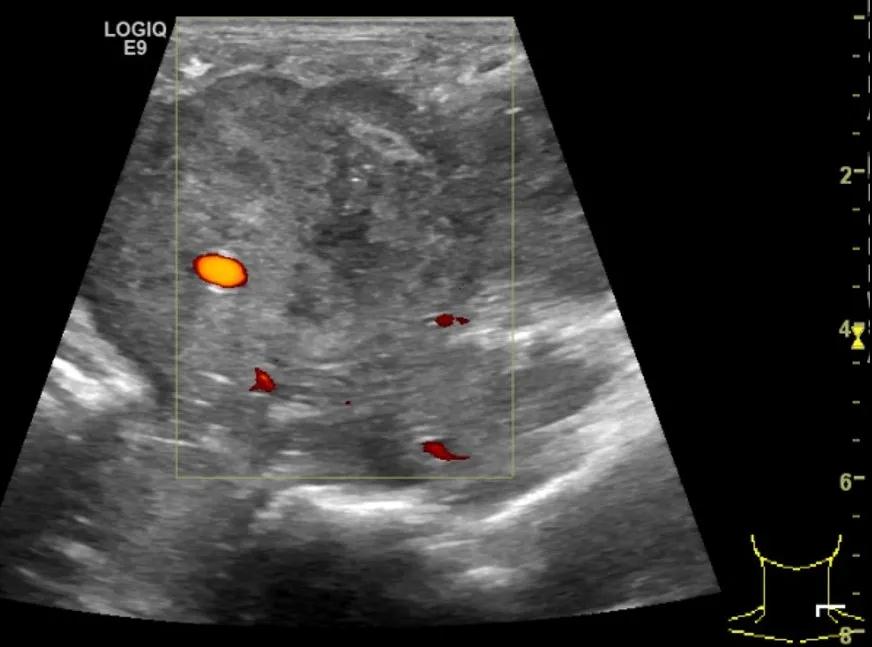

随后,徐栋教授进一步分享了五个临床实战病例,带来了更直观的热消融治疗经验。第一个病例是62岁肺癌患者,术后1年余发现双侧锁骨上淋巴结复发,侵犯神经,存在静脉回流、淋巴回流障碍,肿胀、疼痛非常明显。影像显示患者淋巴结边界不清、形态不规则,存在浸润,血流强化增强。由于患者在系统治疗后进展,且主要目的缓解症状、减瘤。局麻下行热消融术,从后向前逐层消融,热消融之后超声造影即刻评估显示完全充盈缺损,完全覆盖病灶。

(病例1图例)